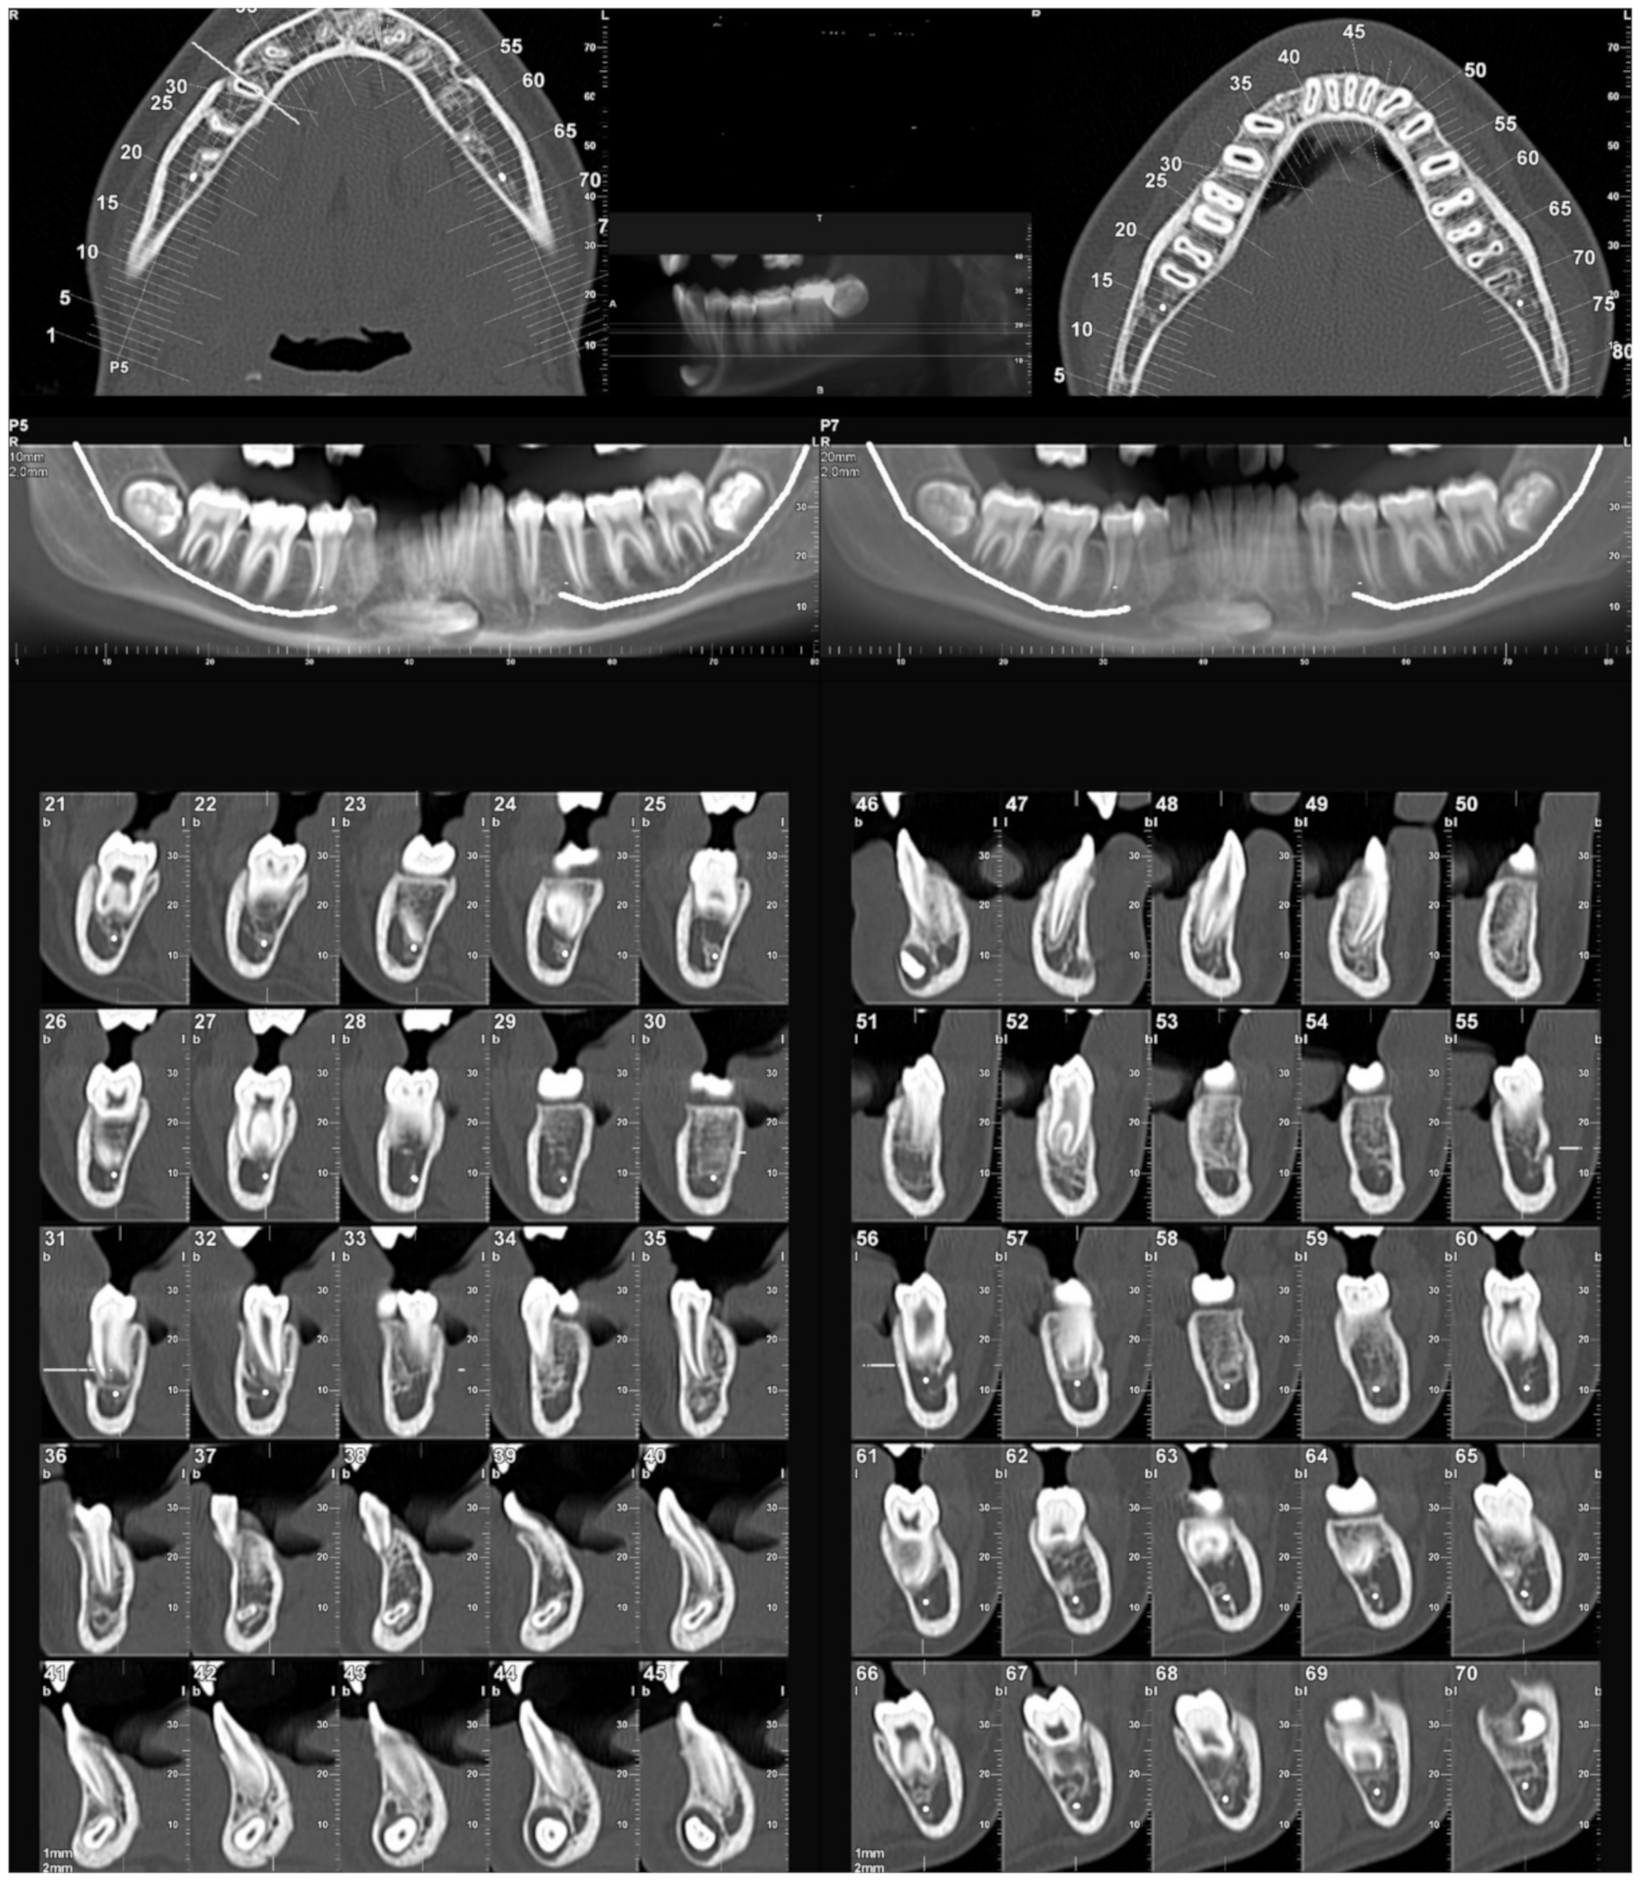

2.3. Evaluation of Radiological Data

- Bertl, M.H.; Frey, C.; Bertl, K.; Giannis, K.; Gahleitner, A.; Strbac, G.D. Impacted and transmigrated mandibular canines: An analysis of 3D radiographic imaging data. Clin. Oral Investig. 2018, 22, 2389–2399. [Google Scholar] [CrossRef] [PubMed]

- Koç, A.; Kaya, S.; Abdulsalam, W.A. Three-Dimensional Analysis of Impacted Maxillary and Mandibular Canines and Evalua-tion of Factors Associated With Transmigration on Cone-Beam Computed Tomography Images. J. Oral Maxillofac. Surg. 2021, 79, 538.e1–538.e11. [Google Scholar] [CrossRef] [PubMed]